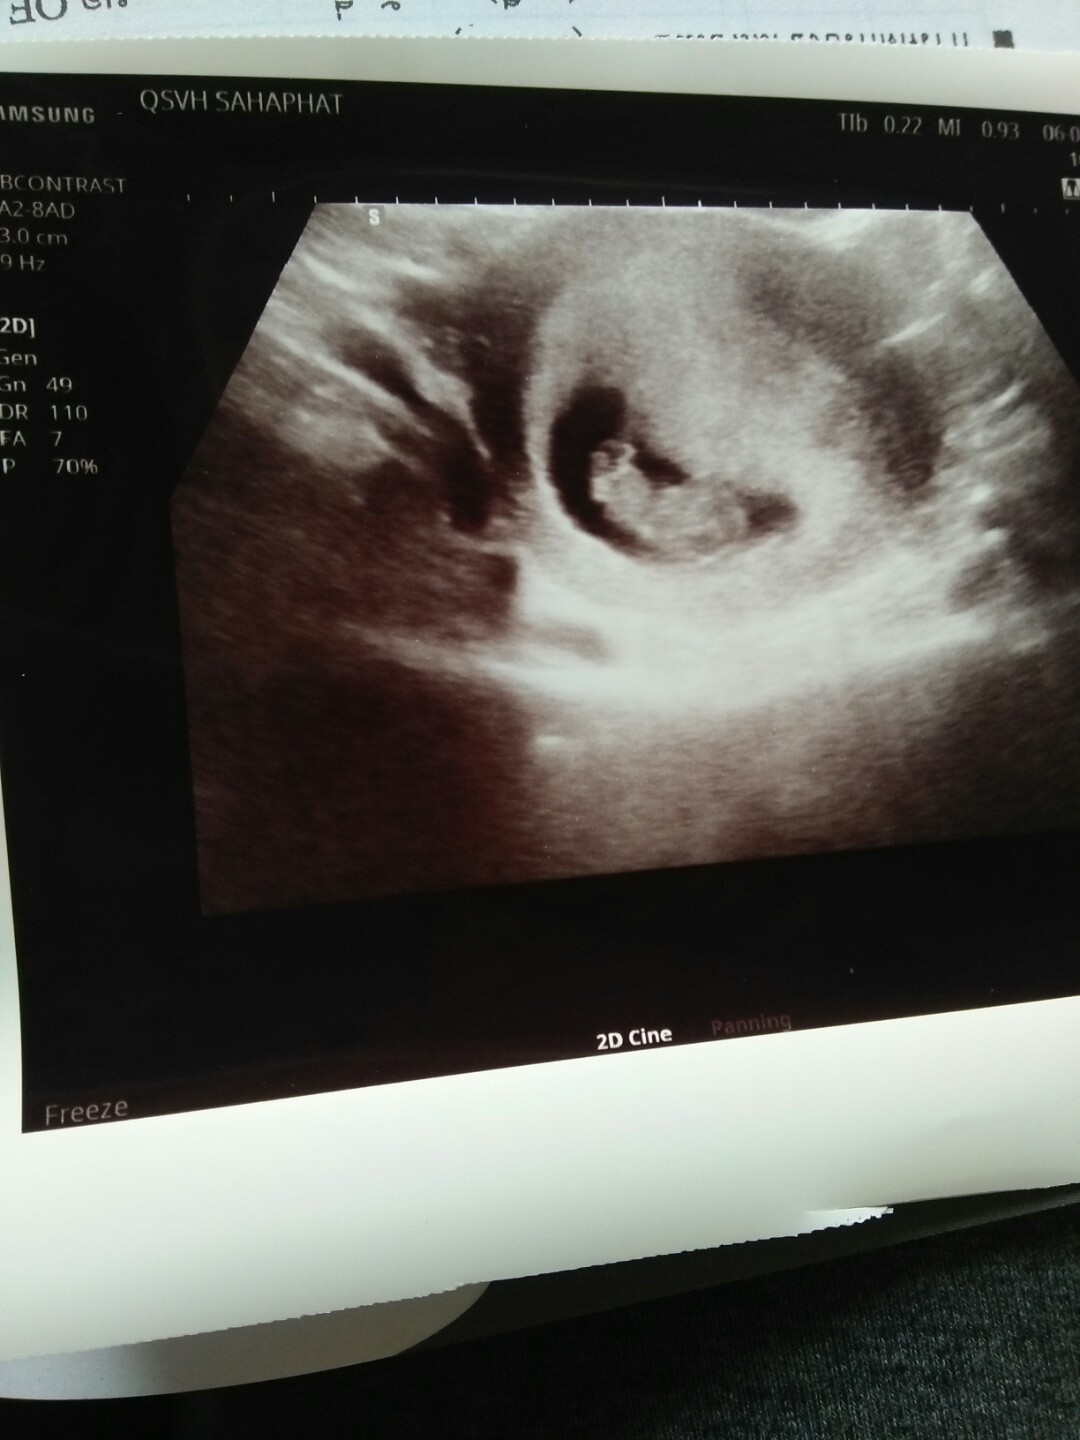

เห็นน้องตอน 4 w ค่ะ